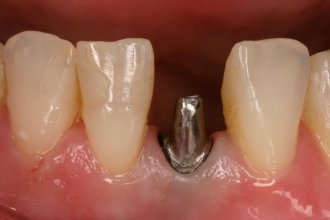

Metallkeramikkrone auf einteiligem Implantat

Untere Frontzähne lassen sich nur mit sehr grazilen Implantaten versorgen. Sie bestehen nur aus einem Stück und müssen deshalb im Mund beschliffen werden. Es lassen sich damit gute Ergebnisse erzielen. Der gräuliche Schimmer im Zahnfleischbereich entsteht, weil das darunterliegende Implantat etwas durchschimmert.